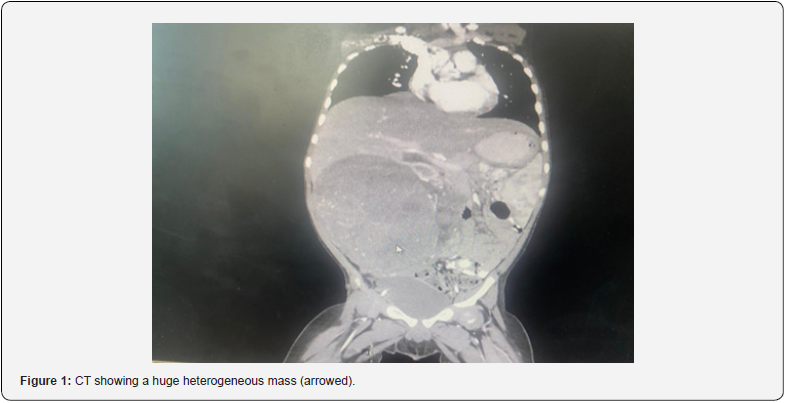

On examination, a palpable mass was identified on the right upper abdomen by his GP doctor and confirmed by the pediatric surgeon doctor as well. The mass was fixed, not mobile, solid, and hard. Ultrasonography imaging was ordered to show a mass measuring 14 cm in maximum diameter across the mid-abdomen. A computed tomography (CT) scan was done that showed a large calcified heterogeneous mass. It also showed stenosis of IVC (Figure 1).